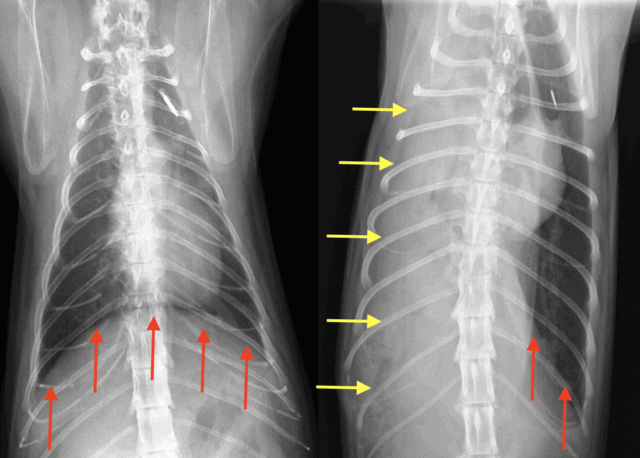

左側のレントゲンは正常な猫ちゃんの胸のレントゲンであり、赤矢印で示す横隔膜のラインがはっきり見えます。

一方、右側のレントゲンはこの猫ちゃんの胸のレントゲンであり、レントゲンの右側では赤矢印で示す横隔膜のラインが見えますが、左側では見えず、黄色矢印で示すお腹の中の臓器が胸の中に入り込んでいます。